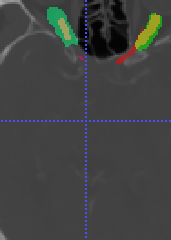

In Chapter 6, we propose an end-to-end, atlas-free 3D convolutional deep learning framework for fast and fully automated whole-volume HaN anatomy segmentation [115]. Our deep learning model, called AnatomyNet, segments OARs from head and neck CT images in an end-to-end fashion, receiving whole-volume HaN CT images as input and generating masks of all OARs of interest in one shot. AnatomyNet is built upon the popular 3D U-net architecture, but extends it in three important ways: 1) a new encoding scheme to allow auto-segmentation on whole-volume CT images instead of local patches or subsets of slices, 2) incorporating 3D squeeze-and-excitation residual blocks in encoding layers for better feature representation, and 3) a new loss function combining Dice scores and focal loss to facilitate the training of the neural model. These features are designed to address two main challenges in deep-learning-based HaN segmentation: a) segmenting small anatomies (i.e., optic chiasm and optic nerves) occupying only a few slices, and b) training with inconsistent data annotations with missing ground truth for some anatomical structures. We collect 261 HaN CT images to train AnatomyNet, and use MICCAI Head and Neck Auto Segmentation Challenge 2015 as a benchmark dataset to evaluate the performance of AnatomyNet. The objective is to segment nine anatomies: brain stem, chiasm, mandible, optic nerve left, optic nerve right, parotid gland left, parotid gland right, submandibular gland left, and submandibular gland right. Compared to previous state-of-the-art results from the MICCAI 2015 competition, AnatomyNet increases Dice similarity coefficient by 3.3% on average. AnatomyNet takes about 0.12 seconds to fully segment a head and neck CT image of dimension , significantly faster than previous methods. In addition, the model is able to process whole-volume CT images and delineate all OARs in one pass, requiring little pre- or post-processing. We demonstrate that our proposed model can improve segmentation accuracy and simplify the auto-segmentation pipeline. These contributions are released as an open-source software package called AnatomyNet, which is publicly available555https://github.com/wentaozhu/AnatomyNet-for-anatomical-segmentation. Portions of this chapter were published as part of [115].